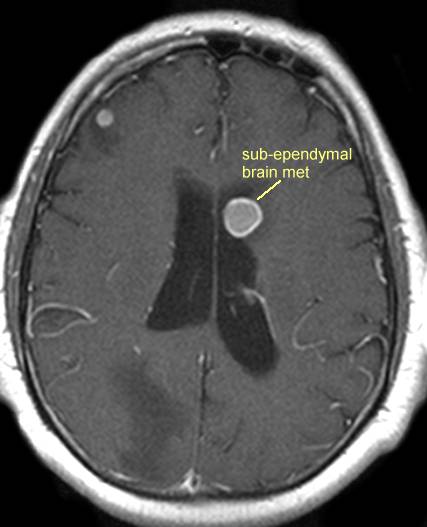

brain_met_midline.jpg (15180 bytes)

unusual metastases to the midline in the third ventricle, from lung cancer